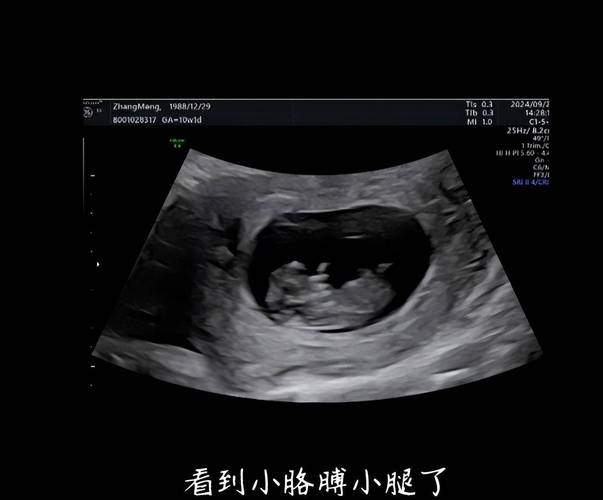

第一次系统排畸B超(NT检查,孕11-13周+6天)

- 测量NT(颈项透明层厚度):这是评估胎儿是否患有唐氏综合征等染色体异常风险的重要指标之一。

- 检查鼻骨:鼻骨缺失也与某些染色体异常有关。

- 初步观察胎儿结构:看头、躯干等大的结构是否正常。

- 核对孕周。

- 重要性:这次检查有严格的时间要求,必须在孕11周到13周零6天之间完成。